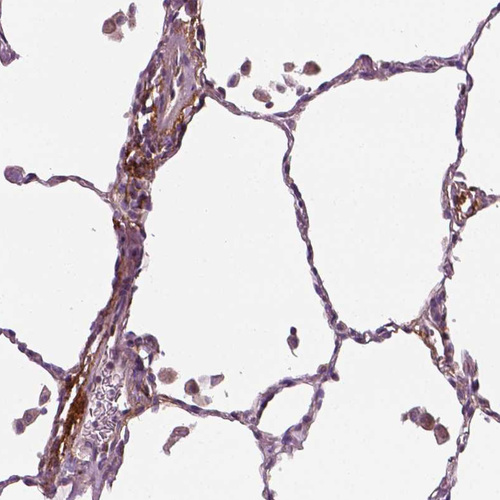

Immunohistochemical staining of human placenta shows moderate cytoplasmic positivity in endothelial cells.